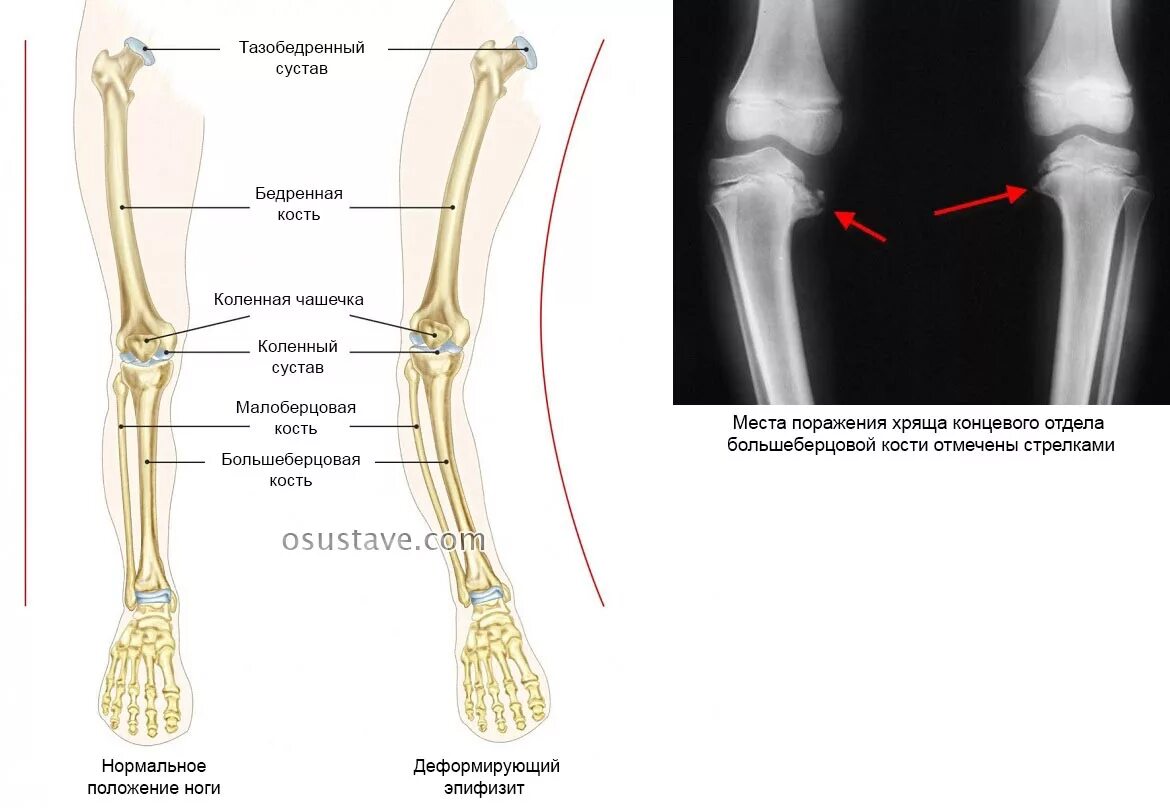

Вальгусная деформация коленных суставов у ребенка